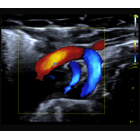

マウス心臓のドップラー像

マウス大動脈弓の血流